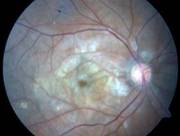

Confluent hemorrhages are the most prominent ophthalmoscopic feature of an acute ischemic central retinal vein occlusion These hemorrhages occur in a wide variety of shapes and sizes; they are usually concentrated in the posterior pole, but may be seen throughout the retina. Many hemorrhages are flame shaped, reflecting the orientation of the nerve fibers. Dot and punctate hemorrhages are interspersed and indicate involvement of the deeper retinal layers. Bleeding may be extensive, erupting through the internal limiting membrane to form a preretinal hemorrhage or extending into the vitreous. Small dot hemorrhages may be seen either isolated or clustered around small venules. The entire venous tree is tortuous, engorged, dilated, and dark. The retina is edematous, particularly in the posterior pole; some of this edema may obscure portions of the retinal vessels. Cotton-wool patches (soft exudates) are often present. The disc margin is blurred or obscured, and the precapillary arterioles appear engorged. Splinter hemorrhages and edema are present on the disc surface and extend into the surrounding retina. The physiologic cup is filled, and the venous pulse is absent. The arterioles, often overlooked because of the other more striking pathologic features, are frequently narrowed. Sometimes in central retinal vein occlusion of acute onset, the fundus picture is less dramatic, and all of the findings previously discussed may be present, but to a lesser degree. Vision depends on extent of macular involvement